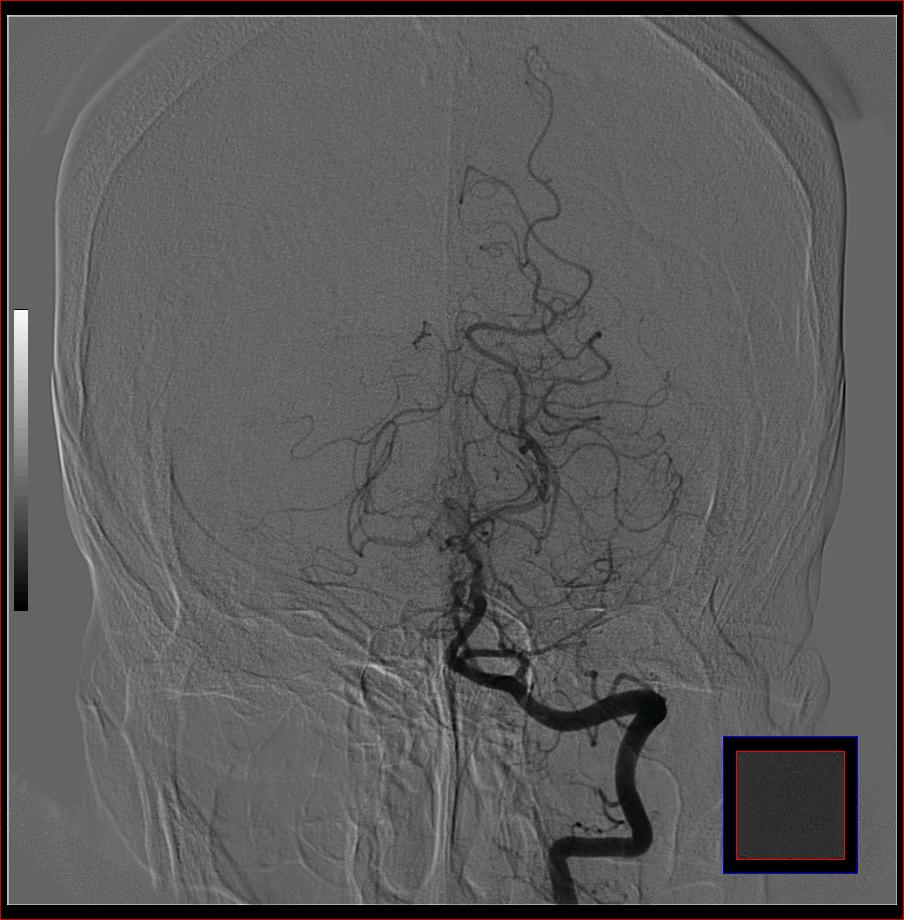

标题: DSA0121:脑血管造影

男,65岁,肢体无力。

左侧大脑中动脉水平段狭窄.

右侧大脑前a缺如.左侧大脑中动脉m1段狭窄,远端分支分布稀疏.

右侧大脑前a缺如.左侧大脑中动脉m1段狭窄

前交通或稍远端动脉瘤要仔细查,左大脑中动脉狭窄要鉴别,有可能是痉挛,因为造影导管插得稍深啦。其它就是供血动脉变异较大

烟雾病